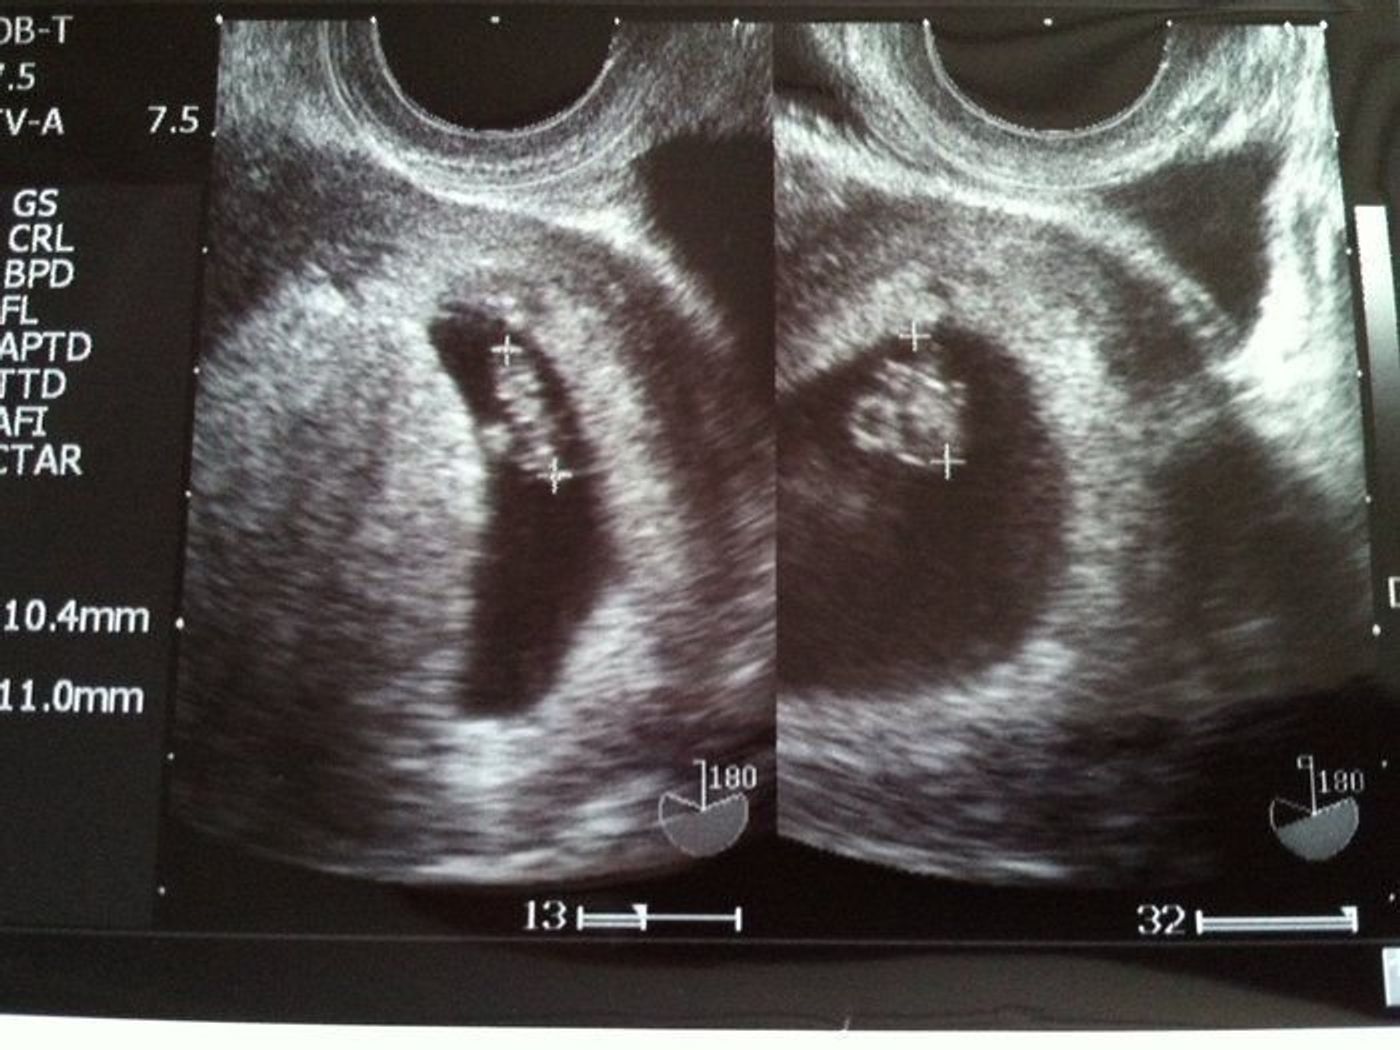

7週 初回検診で双子妊娠が判明 心拍も二人分確認ができました Taekoのocへいこう

妊娠7週 双子発覚 アラフォー双子妊娠 超ハイリスク妊娠生活

双子 隠れていた